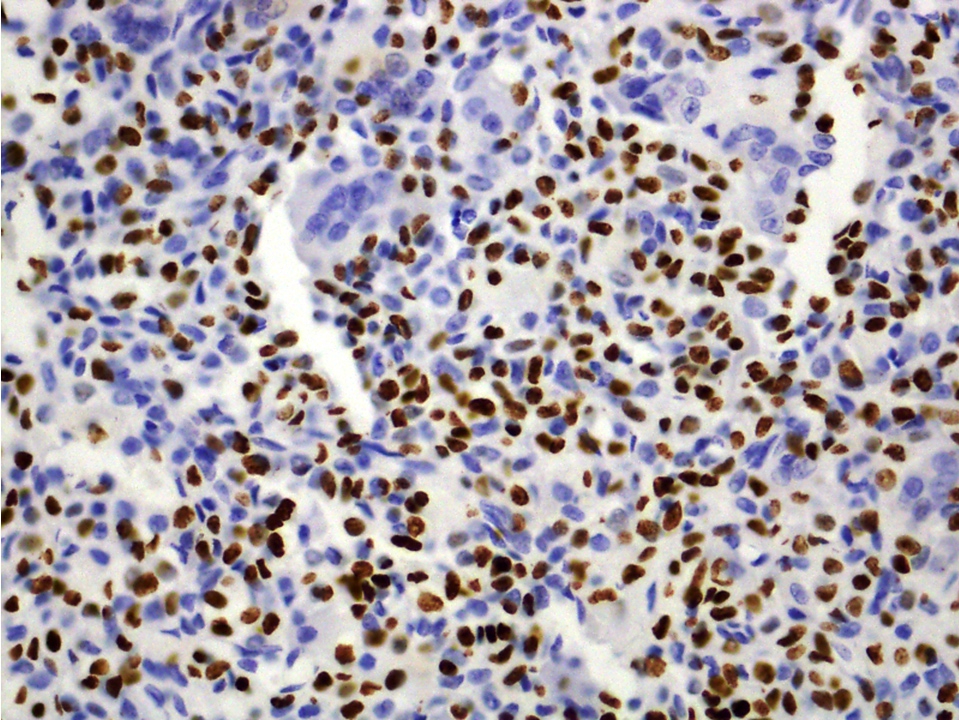

Positive stains

- H3.3B (H3F3B) p.Lys36Met (K36M): diffuse nuclear staining may be helpful to distinguish from aneurysmal bone cyst (Cancer Cytopathol 2018;126:552)

- S100, DOG1 (Ann Diagn Pathol 2020;44:151440)

- SOX9 (Hum Pathol 2010;41:208)